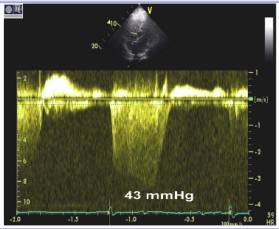

12、三尖瓣收缩期返流峰值流速—TR

●PA压力增高:TR压差+RA压

●PA平均压的准确评估